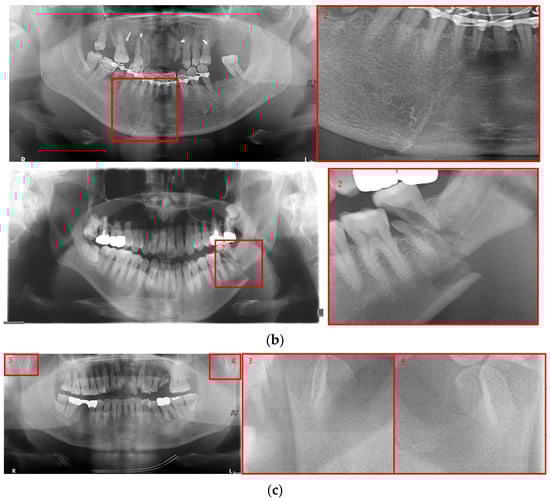

Deep learning networks such as Mask R-CNN, YOLOv4, and U-Net have been used to detect mandibular fractures using only panoramic images. The advantages of the three networks can be identified experimentally through panoramic mandibular fracture images. First, Mask R-CNN specifically marks the fracture area; however, it also marks fractures in areas that are not fractured, such as dark shaded areas in the panoramic image or gaps between teeth; therefore, the false diagnosis rate is higher than that in other deep learning networks. In YOLO, the location information for the six classes divided into anatomical structures is helpful to detect mandibular fractures. However, there are some undiagnosed fracture areas, other than the fractures of the condyle and coronoid process with clear characteristics and location. Unlike the above two deep learning networks, U-Net performs training by labeling fracture and panoramic images. When creating training fracture labeling data, the dislocated fracture area of the condyle fracture is difficult to label. Unlike YOLO, the side fracture area is weak, causing an increase in the misdiagnosis rate when learning by labeling a dislocated fracture. In Figure 17, the mandibular fracture detection results images of LAT YOLOv4 and U-Net with LAT YOLOv4 are compared. The panoramic images in the first and second rows demonstrate the advantages of YOLO and U-Net. While YOLO detects condyle dislocation fractures well, it does not detect angle fractures; however, U-Net detects angle fractures well. The panoramic images in the third and fourth rows show that the undiagnosed area is reduced by using U-Net for the angle area that the LAT YOLOv4 module does not diagnose. Because U-Net performs semantic segmentation, it is advantageous for the segmentation of fractures spread over a wide area. Consequently, the undiagnosed case in the middle of the mandible, where LAT YOLOv4 is weak, is somewhat supplemented by the U-Net module.

Figure 17.

The comparison of LAT YOLOv4 and U-Net with LAT YOLOv4 detection results. (a) LAT YOLOv4 (with red boxes), and (b) U-Net & LAT YOLOv4 (with red boxes and lines).